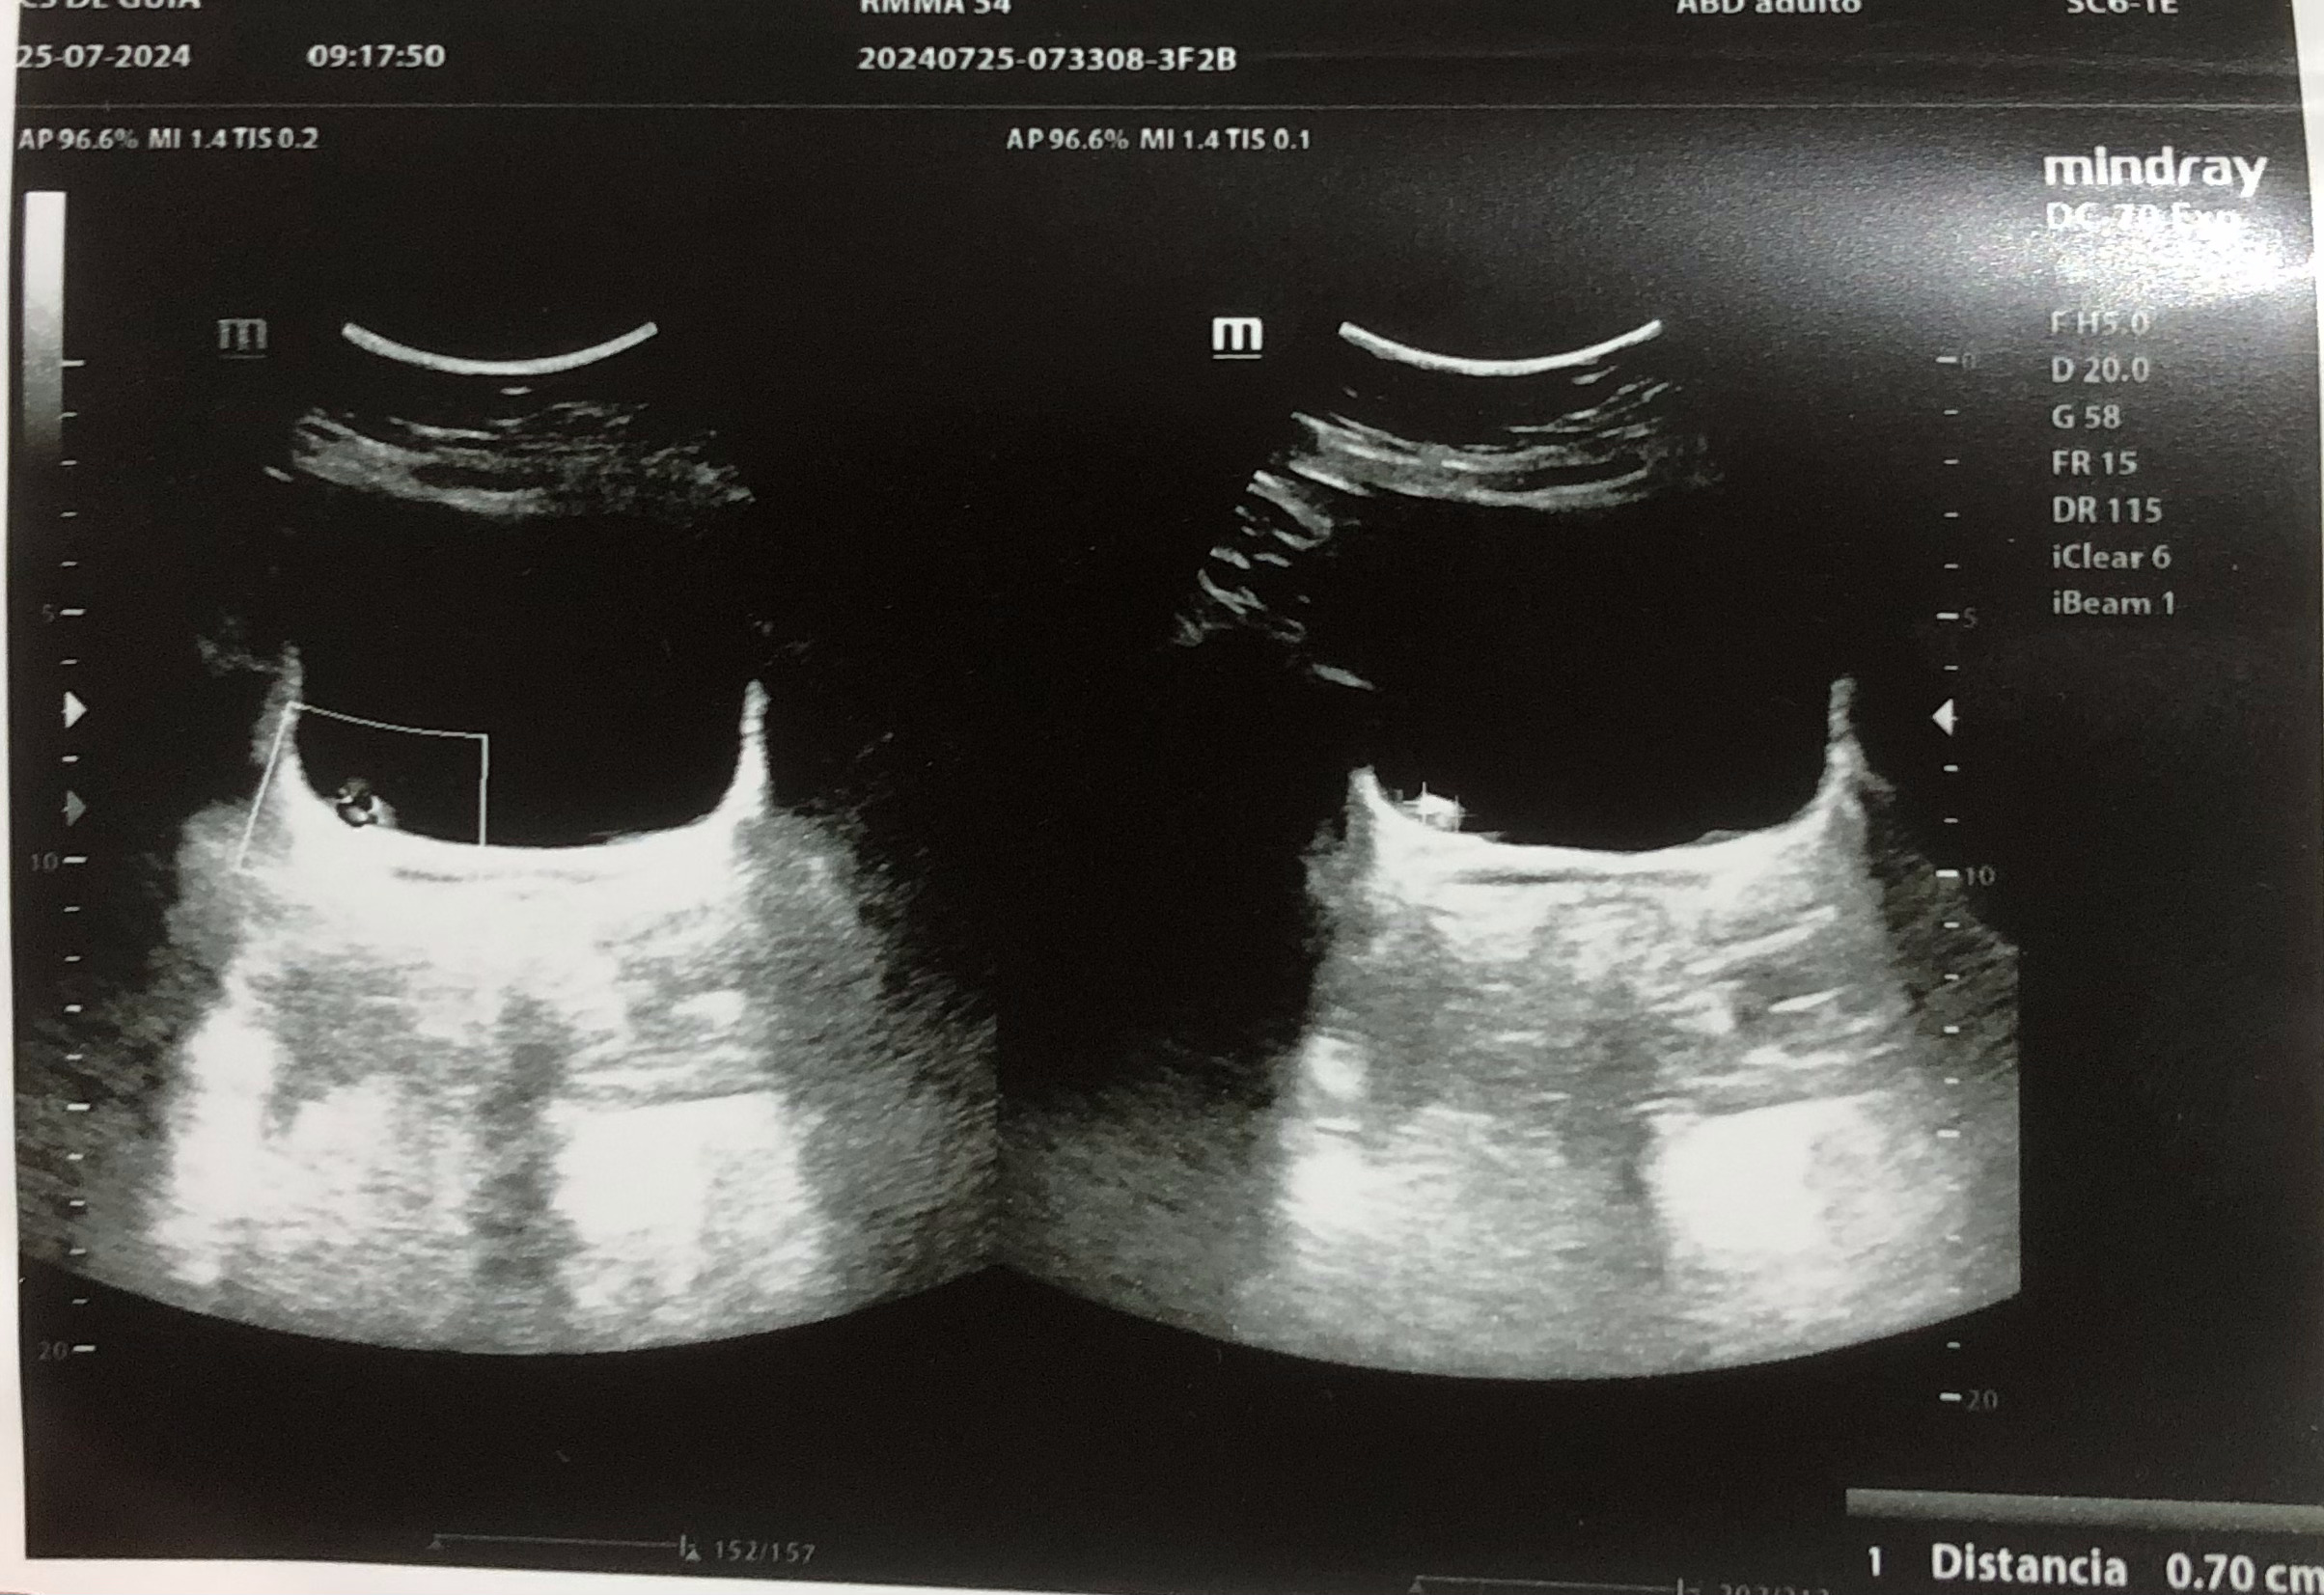

Se realiza ecografía renal donde se aprecia lesión hiperecogénica redondeada en pared inferior derecha de vejiga sin sombra posterior de 0,7 x 0,61 cm, que no se moviliza con cambios posturales de la paciente. Centelleo dudoso.